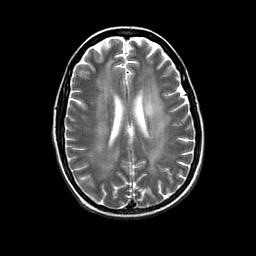

МРТ головного мозга. Аксиальная Т2-взвешенная МРТ. Герпетический энцефалит.

МРТ головного мозга играет ключевую роль в выявлении, оценке распространения и прослеживания динамики герпетического энцефалита. При МРТ головного мозга типичные черты герпетического энцефалита: высокий сигнал от височной доли на Т2-взвешенных МРТ, чаще одностороннее поражение. Поскольку эта зона на МРТ соответствует области Вернике, то у пациента наблюдается афазия и другие речевые расстройства. На МРА нарушений проходимости сосудов не отмечается. МРТ в СПБ при герпетическом энцефалите проводится как в условиях стационара при тяжелом состоянии, так и амбулаторно, в том числе в открытом МРТ. Центры МРТ СПб не имеющие опыта МРТ головного мозга при инфекционных заболеваниях нередко принимают их за опухоли, что ведет к неверной тактике лечения.